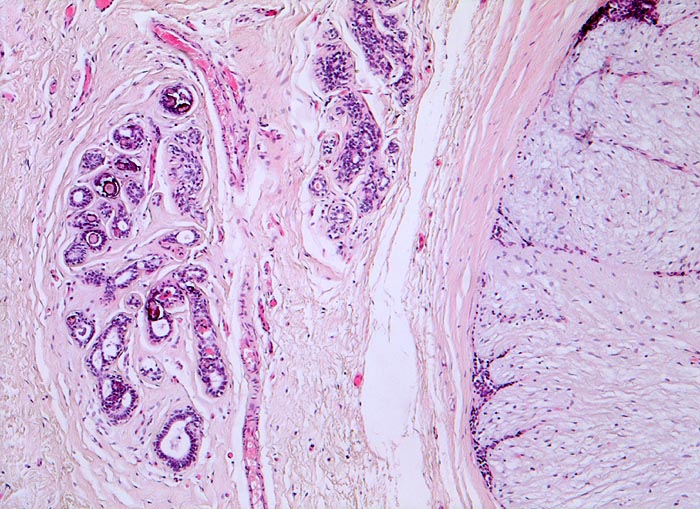

PathoPic – image database / PathoPic ID 3539 - Fibroadenom der Mamma. Mikroverkalkungen.

Fibroadenom der Mamma. Mikroverkalkungen.

Rechts im Bild das scharf begrenzte Fibroadenom bestehend aus reichlich zellarmem Stroma und komprimierten von Epithel ausgekleideten Gängen. Links davon leicht fibrosierte Drüsenläppchen, welche intraazinäre Mikroverkalkungen enthalten.

Scharf begrenzter frei beweglicher 3cm grosser derber Knoten im oberen äusseren Quadranten.

Mikroverkalkungen können auch in nicht neoplastischem Mammaparenchym auftreten, sind also nicht zwingend mit einem in situ Karzinom oder einem invasiven Karzinom assoziiert.